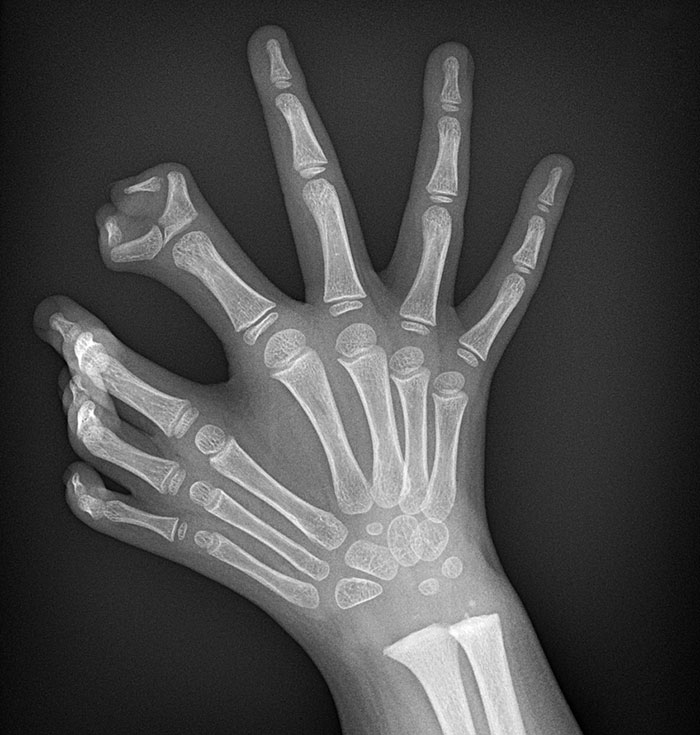

Polydactyl Claw X-Ray